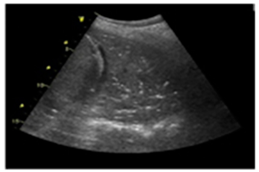

| Acute and chronic HF | Hyperechoic vertical lines extend from the pleural line (which is not thickened) and radiate towards the edge of the echocardiographic field. | ![]() |